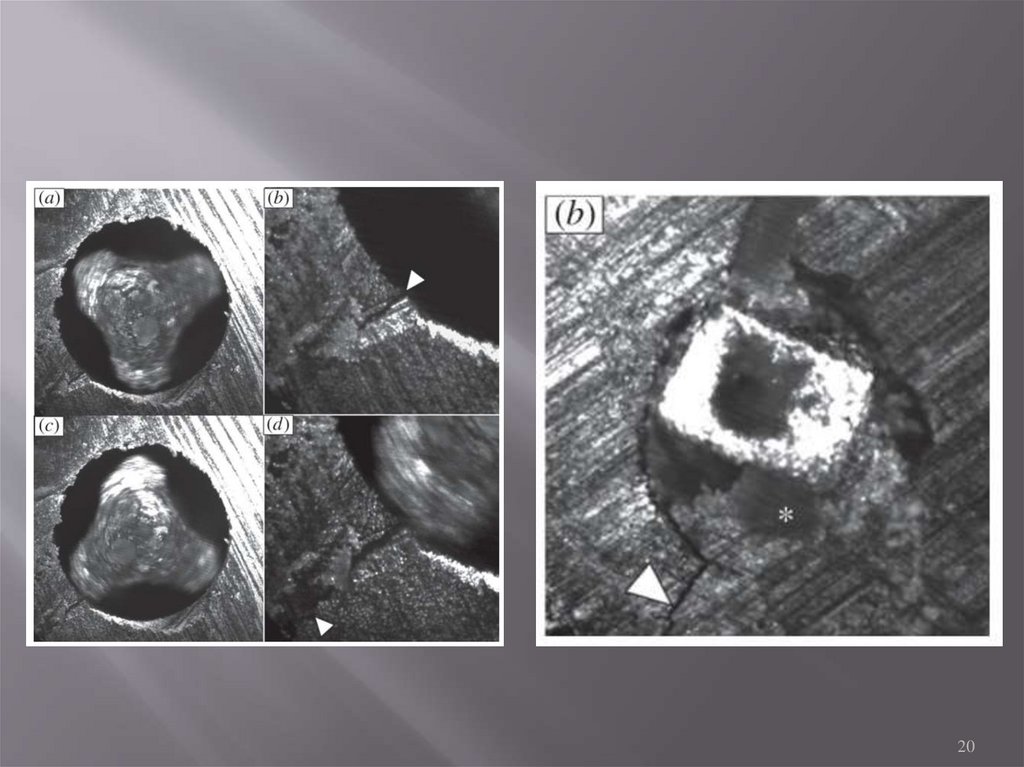

20.

20